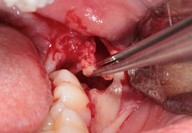

Galleria fotografica